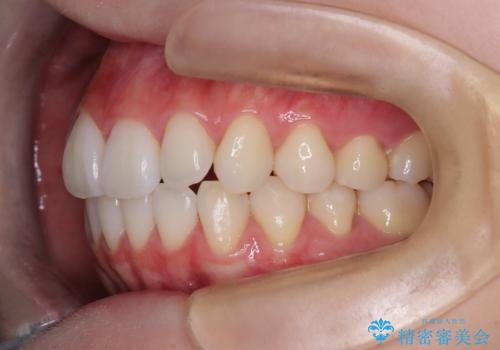

【インビザライン】前歯のねじれを治したい。

- 前歯の凸凹を主訴に来院されました。

スペースを作るために顎間ゴムを使用して、奥歯の遠心移動をおこない配列しました。

奥歯の遠心移動を行うことで、犬歯関係も良い状態に仕上げることができました。